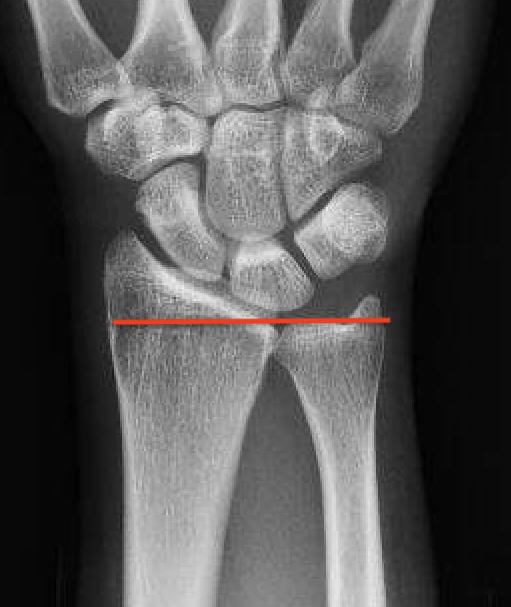

| Stage II | Stage IIIA |

|---|---|

| Sclerosis |

Collapse / fragmentation Normal carpal height |

![]() |